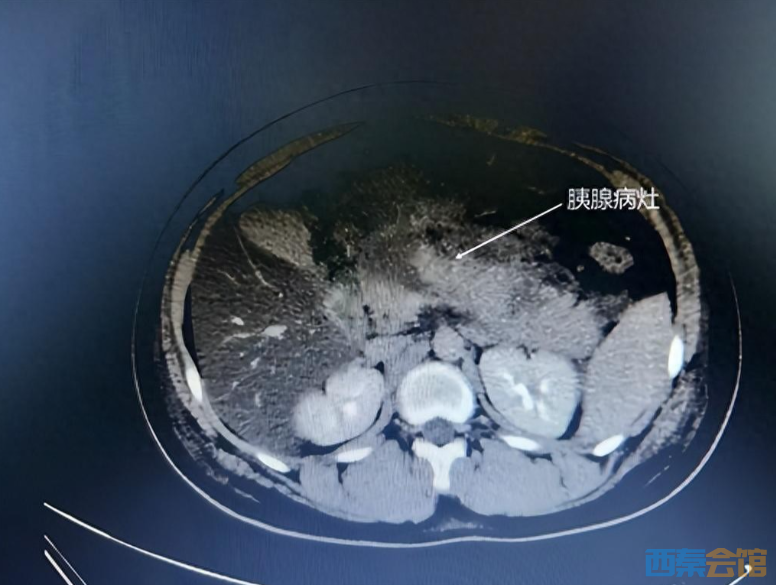

复查全腹CT显示“胰腺组织肿胀明显,大面积坏死,周围见皂化钙化斑块”,炎症指标严重超标(PCT更是远超上限值0.05ug/L的30倍)。在积极的“抗感染、抑酸、生长抑素及镇痛”联合治疗下,休克情况明显好转,但相关炎症和淀粉酶指标持续升高,腹痛等症状仍无法得到控制。

“这属于急性重症坏死性胰腺炎的典型表现,即便采取积极的手术治疗,临床病死率依旧较高,医患双方都面临着巨大的风险与挑战。”医生为患儿紧急实施机器人辅助腹腔镜下胰腺病灶清除、引流术,终将小杰从死亡线上拉了回来。